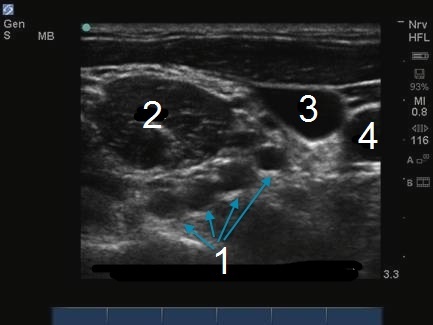

M-Turbo:腕神経叢斜角筋間レベル4

腕神経叢–斜角筋間レベル

MSM

JV

CA